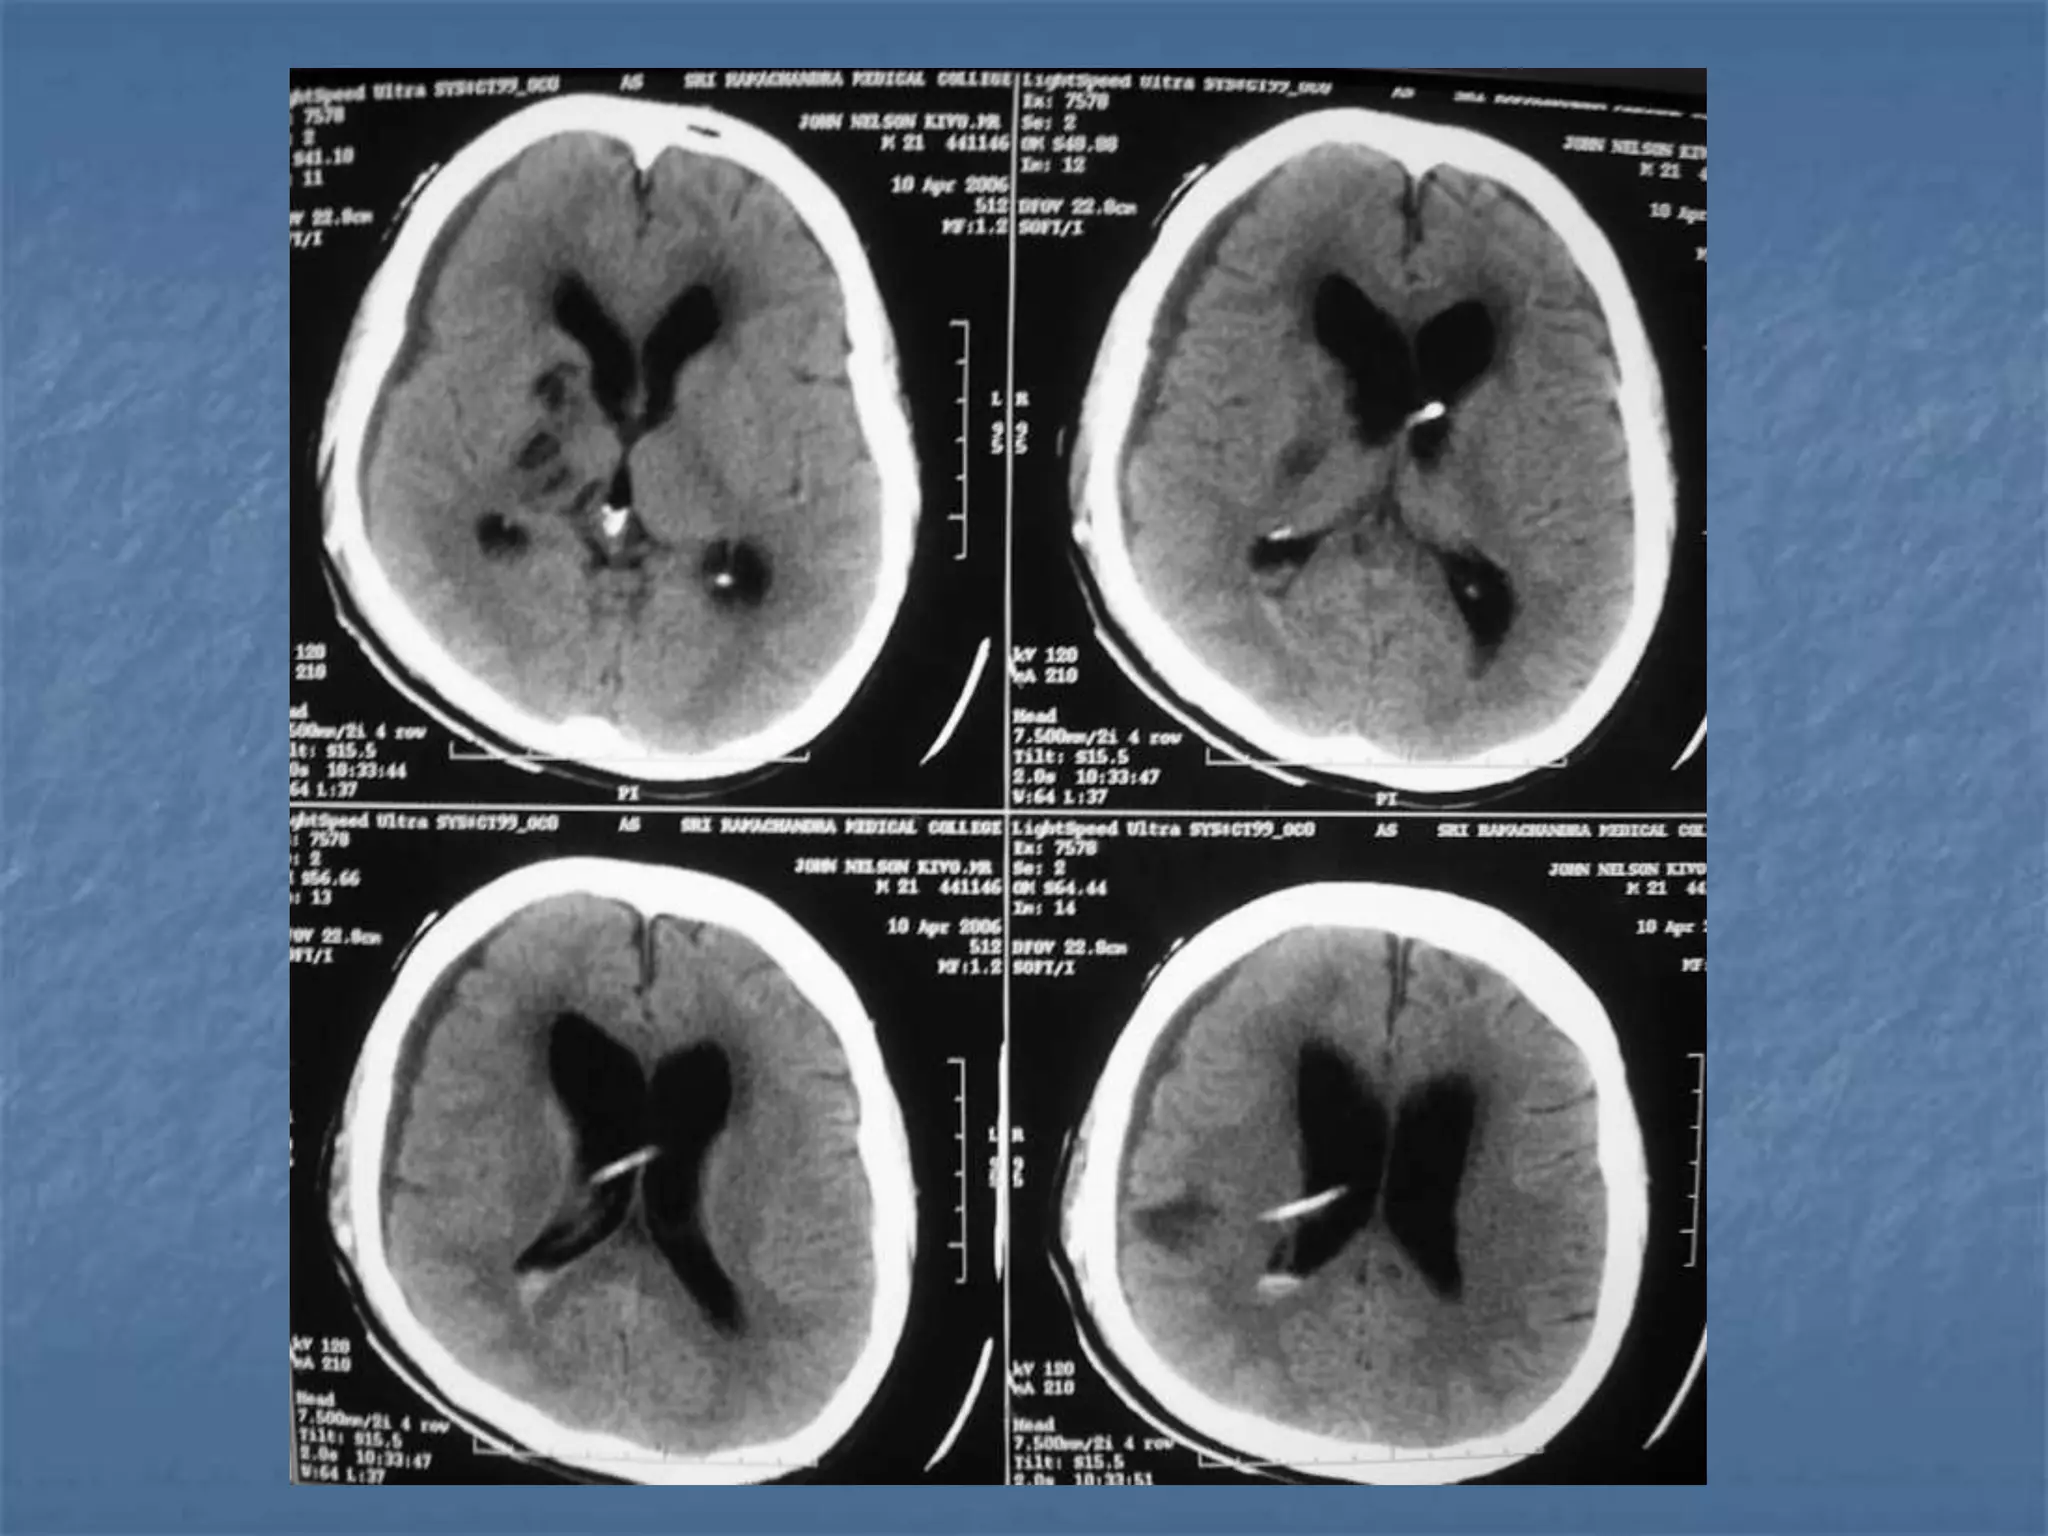

SUBACUTE SDH

ACUTE ON CHRONIC SDH

CONTUSION SAH

Epidural Hematoma

 An epidural hematoma is usually associated with a skull

fracture. It often occurs when an impact fractures the

calvarium. The fractured bone lacerates a dural artery or a

venous sinus. The blood from the ruptured vessel collects

between the skull and dura. On CT, the hematoma forms a

hyperdense biconvex mass. It is usually uniformly high

density but may contain hypodense foci due to active

bleeding. Since an epidural hematoma is extradural it can

cross the dural reflections unlike a subdural hematoma.

However an epidural hematoma usually does not cross

suture lines where the dura tightly adheres to the adjacent

skull